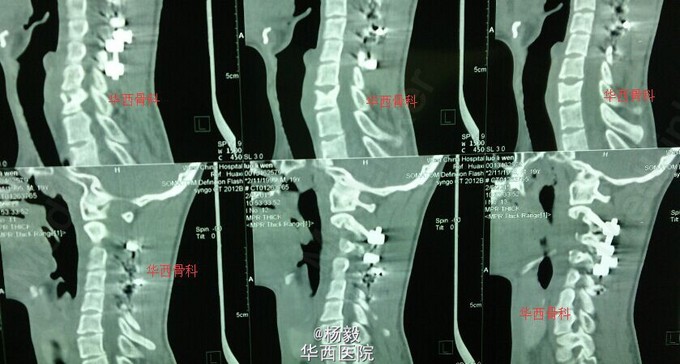

原创病例分享:颈椎结核术后1年余,门诊复诊。

颈椎结核

患者青年男性,20岁,术前椎管内冷脓肿,刘浩教授主刀手术,椎板切除后融合,继续抗结核治疗,门诊复诊。 欢迎大家讨论颈椎结诊断、治疗。